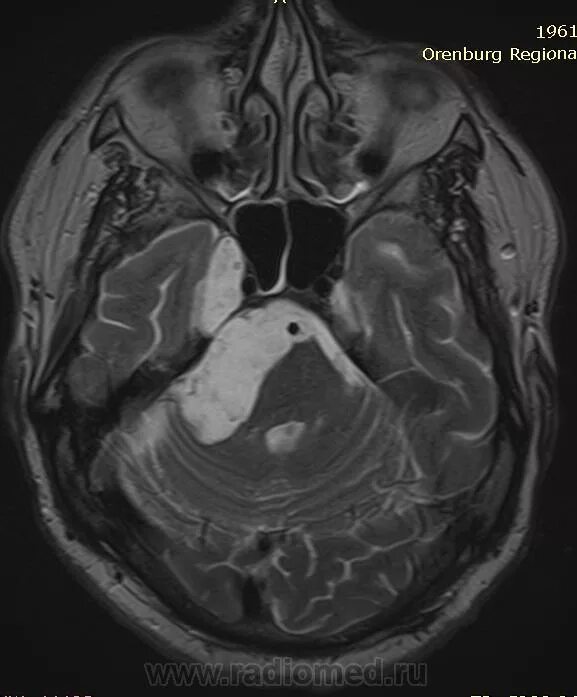

Мрт головного мозга мосто мозжечкового угла